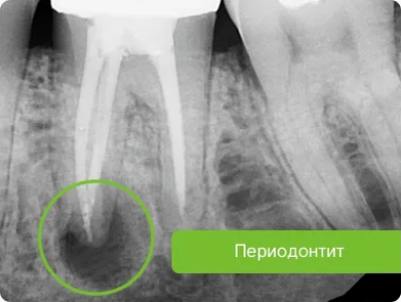

Периодонтит – воспаление комплекса соединительных тканей (периодонта), окружающих корень зуба.

Для диагностики периодонтита проводят осмотр полости рта, сбор анамнеза, рентгенологические исследования.